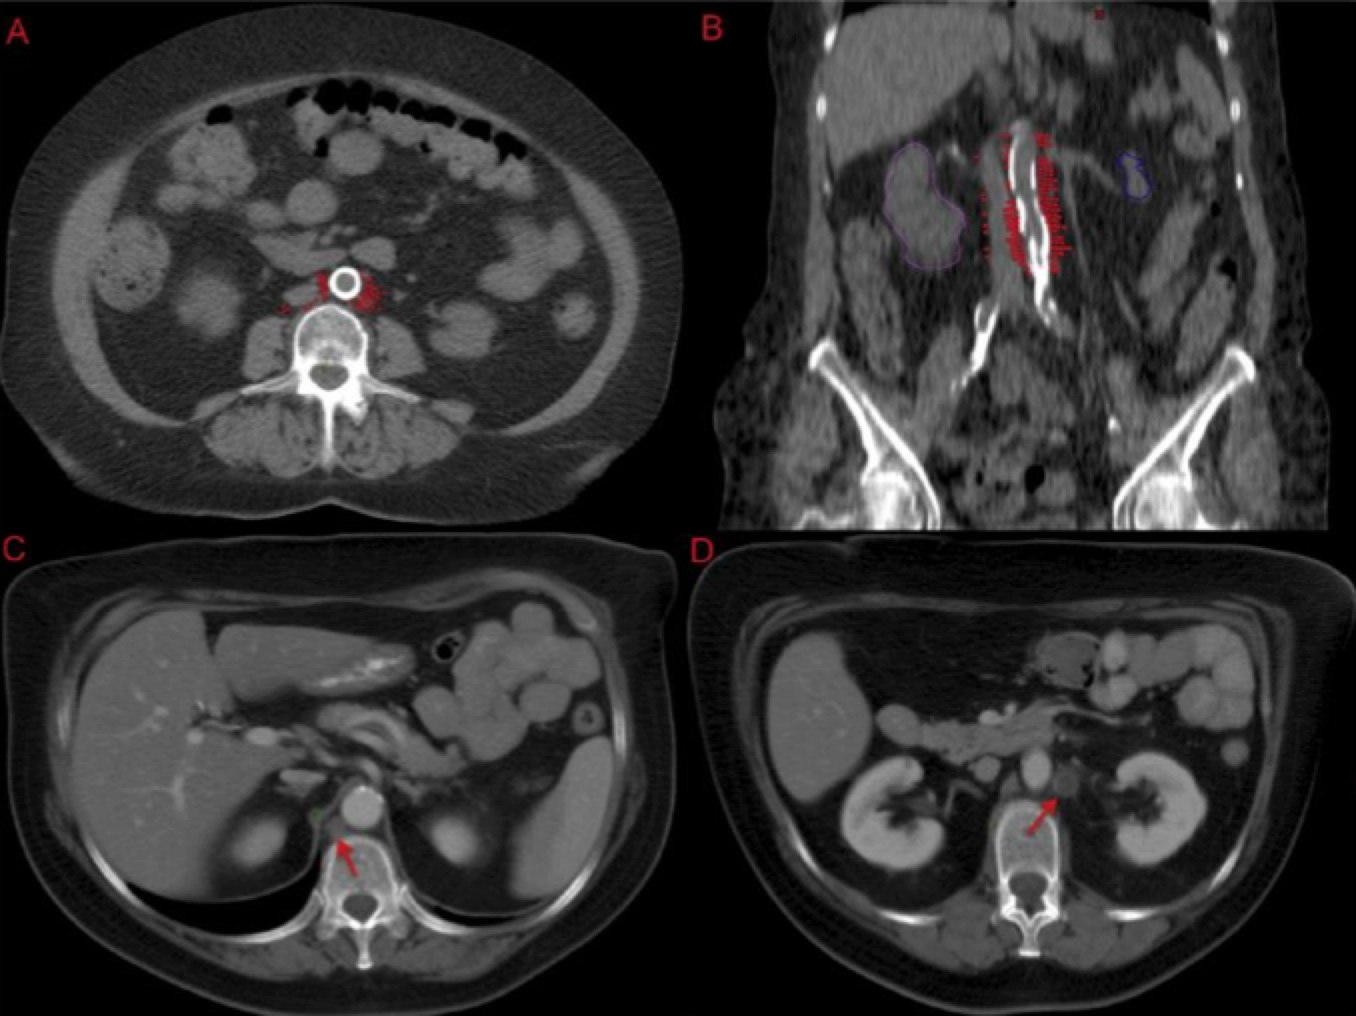

To identify the obturator nodes the following landmarks may be used. (Note: this works for any pelvis where one wishes to find the obturator nodes):